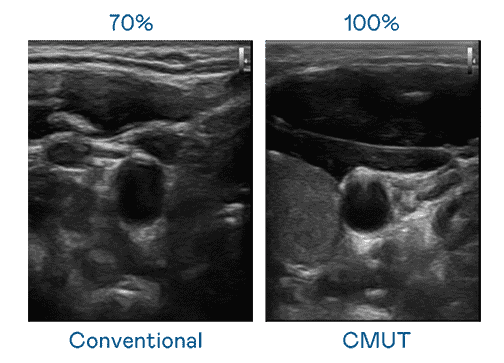

CMUT 技术是一种用电容式微机电元件来产生超音波讯号的技术。。。。与传统 PZT 压电式技术相比,,,CMUT 频宽增加 30%,,更宽频的超音波讯号让影像解析度大幅提升,,,是实现高影像品质医疗超音波扫描、、、、促进精准医疗发展的关键技术。。。。

超音波影像的解析度高低,,,,首先取决于探头能发出的讯号频宽。。菠菜论坛 CMUT 可提供高清晰的超音波讯号,,提供高频宽、、、、高灵敏度、、、影像纹理细节更高的超音波影像,,,,协助医护人员缩短影像判读时间及利用精准的医疗影像进行诊断。。